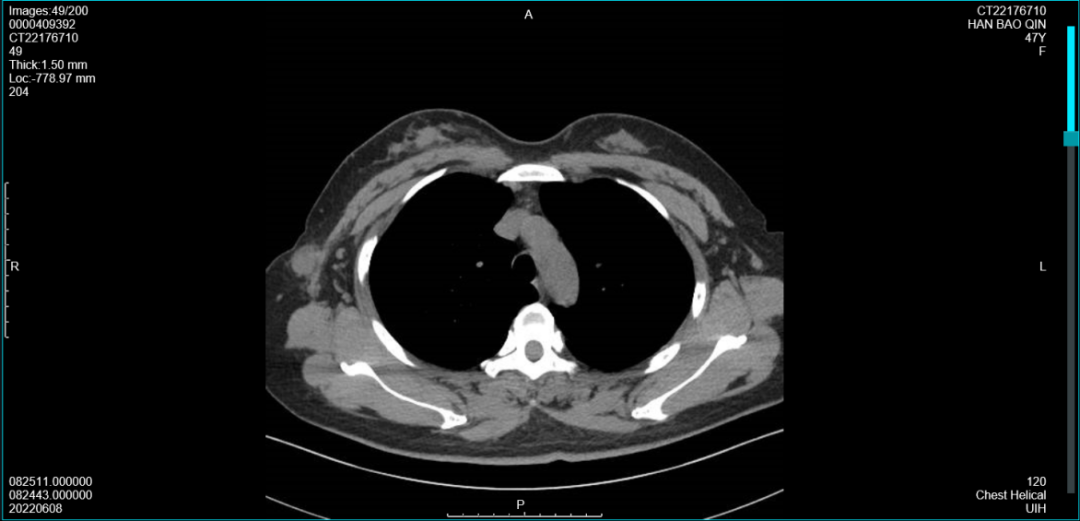

2021年7月14日胸部CT:双肺(-)。未扫及右乳肿块,右腋窝可见数个淋巴结(最大19×17mm)

图5胸部CT见右腋下肿大淋巴结